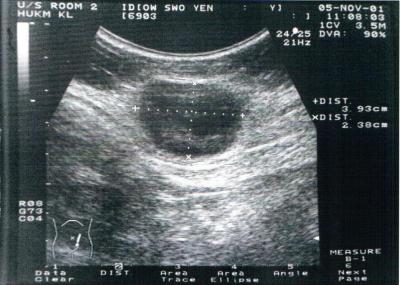

Figure 1:	Ultrasound showed a fairly well defined inhomogenous soft tissue mass, measuring about 4x4x2.6cm in the deep subcutaneous region in left iliac fossa